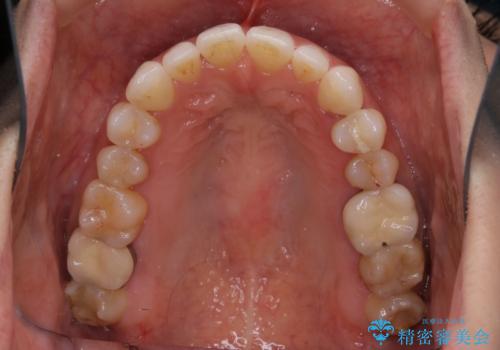

- 前歯のがたつきと反対咬合を主訴に来院されました。

インビザライン・クリンチェック(歯のシミュレーション)を行い、

インビザラインライトで治せる範囲であることを確認し治療を開始することになりました。

今回はクリンチェックを作成したのちに、枚数が少なくても可能であることが判明したためインビザラインライトでの治療を行いました。

最初はインビザラインモデレートパッケージの予定で契約をされていたので、金額も10万円以上安くなり仕上がりも満足頂きました。